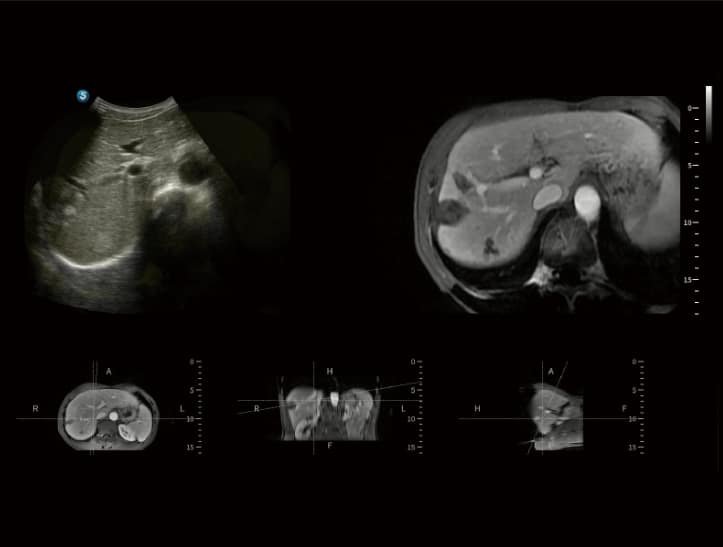

• SonoFusion: Eine wegweisende Technologie, die Ultraschalldaten direkt mit CT- oder MRT-Daten fusioniert, ohne dass externe Sensoren benötigt werden.